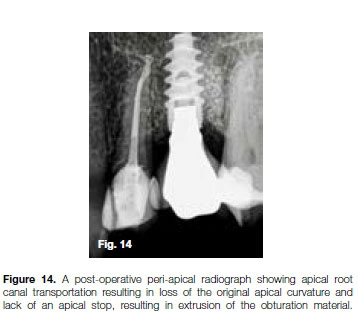

The root canal system was prepared with the Pro-Taper Universal (Dentsply Sirona) system. Incorrect use of the X3 file (30/09) resulted in apical transportation. This was visible on the peri-apical radiograph taken to confirm the cone-fit of the gutta-percha point (Figure 13). After root canal obturation it became more evident that an excessive amount of the root canal wall structure on the outside curve in the apical part of the canal was removed by the rotary file. This resulted in the loss of the original apical curvature, lack of an apical stop and subsequent extrusion of the obturation material (Figure 14).